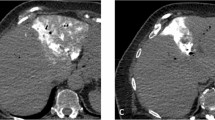

Semi-automated measurements were taken independently by two radiologists (F.G. and M.M.) using two dedicated semi-automated oncology software tools, MintLesion (version 2.6.4; MintMedical, Heidelberg, Germany) and MM Oncology (Syngo.via, Version VB30, Siemens Healthineers, Forchheim, Germany). An example of semi-automated measurement of the longest diameter and volume of liver lesion across all dose levels is showed in Fig. 1. The observers started the semi-automated segmentation process by drawing a circle/diameter over the target lesions on the axial image using the same slice position as the manual measurements were performed. The longest diameter and volume of the liver lesion were automatically calculated by the two different software tools. Each segmented target lesion was verified visually by each observer and manual adjustments could be made with dedicated correction tools if the lesion was not fully included in the segmentation field or if there was too much overlap of adjacent tissue.